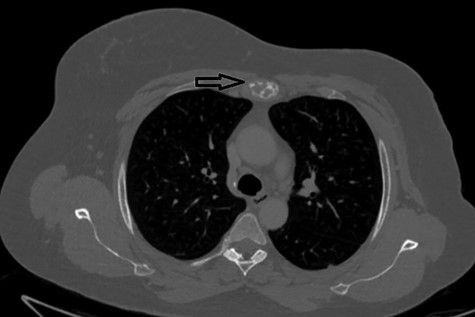

The first case at our institution was a 39-year-old woman who had a history of left breast carcinoma treated with left mastectomy, axillary node clearance and immediate reconstruction under the care of the breast team 3 years prior to presentation. She had no significant co-morbidities. Her past surgical history consisted of the aforementioned oncological operation, appendicectomy and cholecystectomy. She had completed adjuvant oncological therapy in the form of chemoradiotherapy and maintenance hormonal therapy. Her post-operative histology was consistent with a fully excised left breast ductal carcinoma and spread to three out of nine lymph nodes. Due to positive oestrogen receptor-2 status, she had been placed on hormonal therapy. She re-presented with chest wall and sternal pain and subsequent computer tomography (CT) imaging demonstrated a suspicious looking lytic lesion in the mid-sternum (Fig. 1). She underwent a biopsy of this lesion, which confirmed the diagnosis. She had been taking opioid medication for the pain. She was seen in clinic and counselled for partial sternectomy and reconstruction. She underwent partial sternectomy and underwent reconstruction with vertical and horizontal Synthes® plates. Her post-operative recovery was unremarkable. Post-operative histology was consistent with metastatic breast carcinoma completely excised. The recovery was uncomplicated and the patient was seen in clinic with a satisfactory chest radiograph demonstrating the sternal Synthes® plates (Fig. 2).